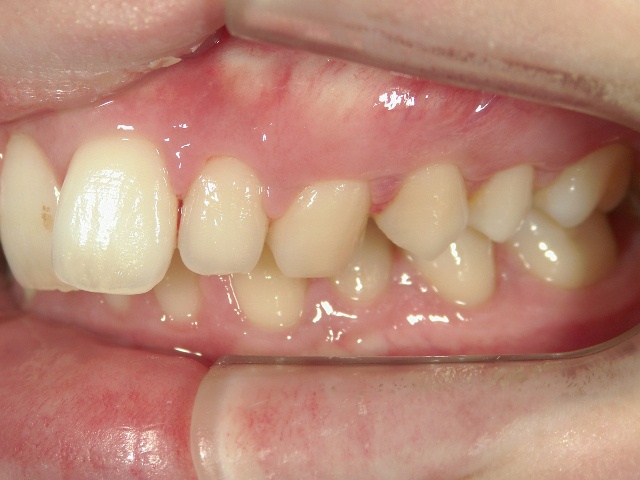

矯正歯科 治療前 左

矯正歯科 治療後 左